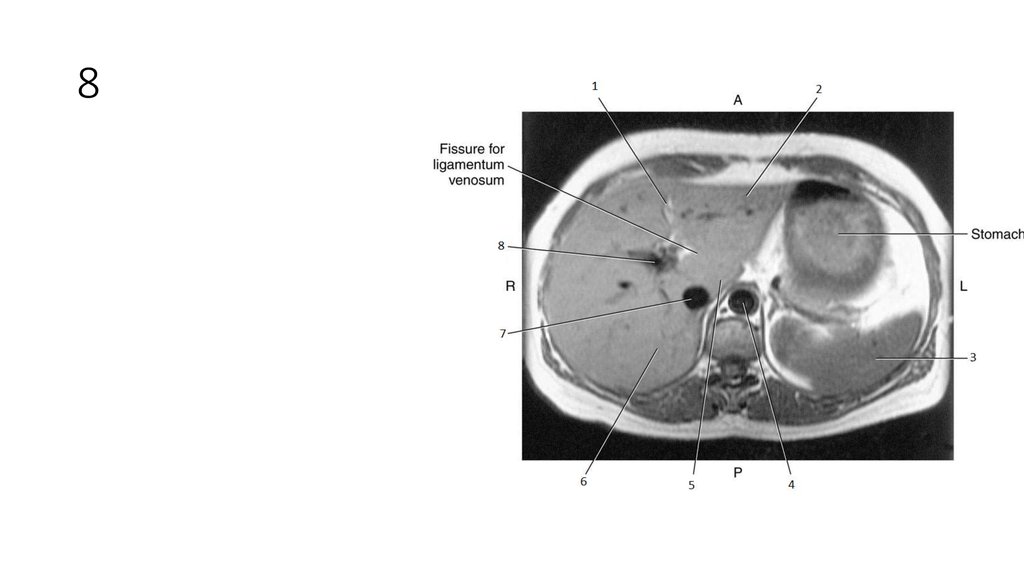

30. 8

31. 8

• Portal Vein

32. 1

33. 1

• Intrahepatic Ducts

34. 2

35. 2

• Pancreatic Duct

36. 3

37. 3

• Common Bile Duct

38. 4

39. 4

• Cystic Duct

40. 5

41. 5

• Common Hepatic Duct

42. 6

43. 6

• Gallbladder